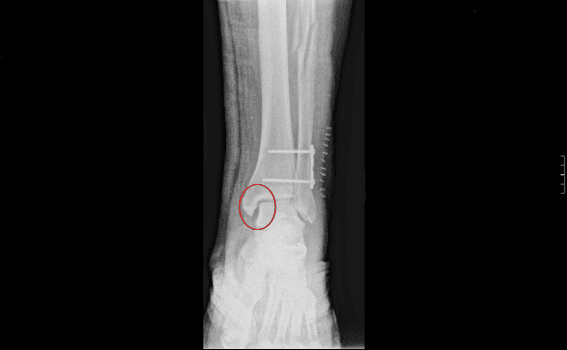

Resumen Este procedimiento quirúrgico se utiliza para corregir una fractura del peroné o de la tibia en la articulación del tobillo El procedimiento consiste en la fijación de una placa de fijación de acero inoxidable o titanio al peroné y el uso de tornillos o placa de fijación en la tibia para estabilizar los huesos y permitir la curación. Por ejemplo, una fractura en el extremo del peroné se llama fractura de maléolo lateral, o si tanto el peroné como la tibia se rompen, se denomina fractura bimaleolar Dos articulaciones están involucradas en las fracturas de tobillo Articulación del tobillo donde se encuentran el peroné, la tibia y el astrágalo Articulación de sindesmosis articulación entre el peroné y la tibia, que se mantiene unida mediante ligamentos. Son indirectos y van a dar lugar a los esguinces de tobillo y a las fracturas maleolares (tibial, peroneo) Traumatismos por compresión axial (indirectos) tenemos las fracturas del pilón tibial (es el segmento distal de la tibia, a nivel supramaleolar) o las fracturas del calcáneo (fractura de los amantes, es la típica del medio laboral).

Muchos pacientes acuden a IICOP, con secuelas de fractura de tobillo, generalmente tipo B y C de WeberEn la mayoria de los casos estas secuelas se han producido por una inadecuada estrategia de tratamiento, en los que se no se han aplicado los principios básicos de reconstrucción anatómica completa de todos los componentes de la articulación. La tibia es el nombre que recibe el hueso más largo de la pierna Su extremo superior presenta dos eminencias óseas que se articulan con los cóndilos femorales que encajan conformando la rodilla, mientras que su extremo inferior forma el maléolo interno o prominencia interna del tobillo. CIE10 Сódigo S para Fractura de la pierna, inclusive el tobillo Incluye maléolos Las siguientes subdivisiones se ofrecen para uso opcional, como carácter suplementario, cuando no es posible o no se desea usar la codificación múltiple para identificar las fracturas con heridas;.

A sus 64 años, Luis vende paletas para atender su fractura de tobillo por lo que ahora requiere el apoyo de la ciudadanía para poder atender la fractura de tibia, peroné y tobillo. Fractura de la extremidad distal de la tibia (fractura de tobillo), esta última pueden ser simple, bimaleolar o trimaleolar Se llaman fracturas del pilón tibial a aquellas que afectan a la extremidad distal de la tibia, es decir al sector de la tibia más próximo al pie, pero por encima de los maleolos. Muchos pacientes acuden a IICOP, con secuelas de fractura de tobillo, generalmente tipo B y C de WeberEn la mayoria de los casos estas secuelas se han producido por una inadecuada estrategia de tratamiento, en los que se no se han aplicado los principios básicos de reconstrucción anatómica completa de todos los componentes de la articulación.